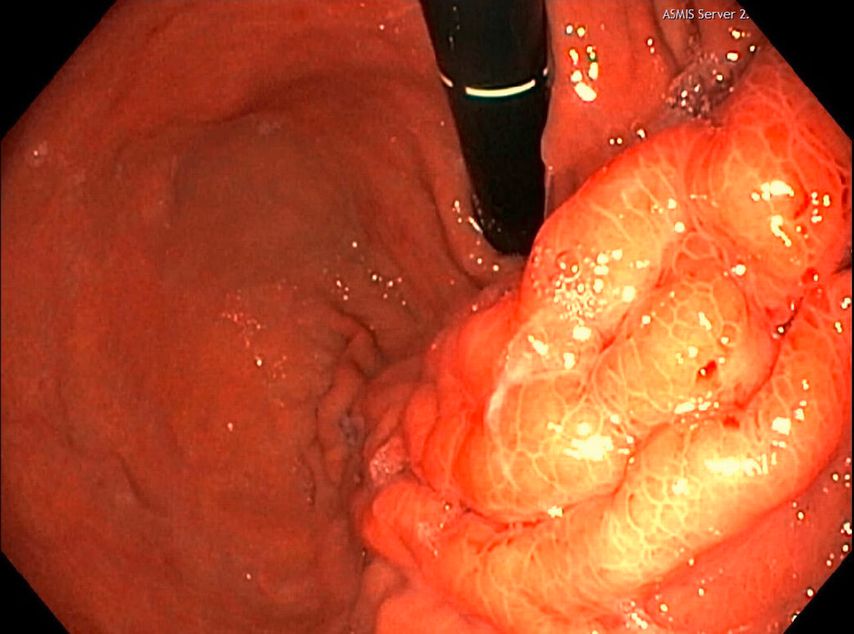

Es folgen eine sonografisch gezielte Punktion und perkutane Pigtail-Drainageanlage in die Fluidokollektion (Abb.3). Prompt entleeren sich 2,8l Pus. Die Drainage wird regelmäßig gespült und für 10 Tage belassen. In der Kultur des Punktats können Streptococcus anginosus und Klebsiella pneumoniae nachgewiesen werden, die initial eingeleitete Antibiose mit Piperacillin/Tazobactam wird antibiogrammgerecht umgestellt. Eine Kontrollgastroskopie (Abb.4) zeigt einen unauffälligen Befund am Pylorus und im Bulbus sowie in der Pars descendens duodeni, zahlreiche Biopsien der Magenschleimhaut ergeben eine geringgradige chronische, inaktive Corpusgastritis mit mukosalem Ödem.